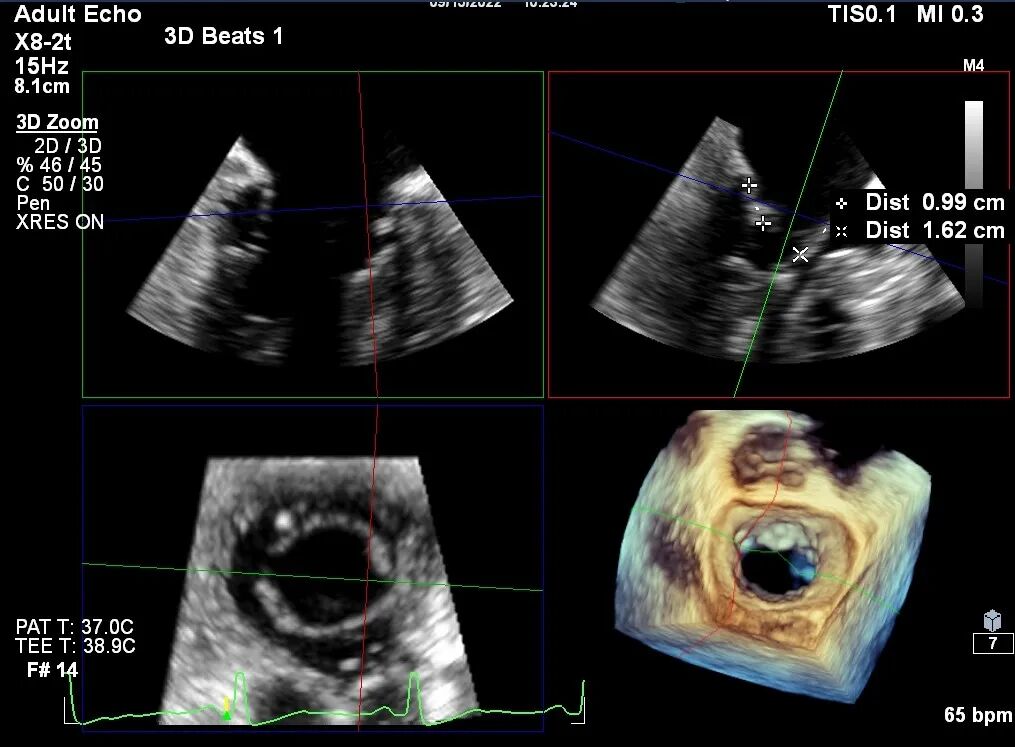

术前TEE评估

原发性MR,交界C1区脱垂,反流程度4+;二尖瓣瓣口面积3.88cm²,平均跨瓣压差2mmHg;二尖瓣前叶(A1)长度16.2mm,二尖瓣后叶长度(P1)长度9.9mm,脱垂高度6mm。